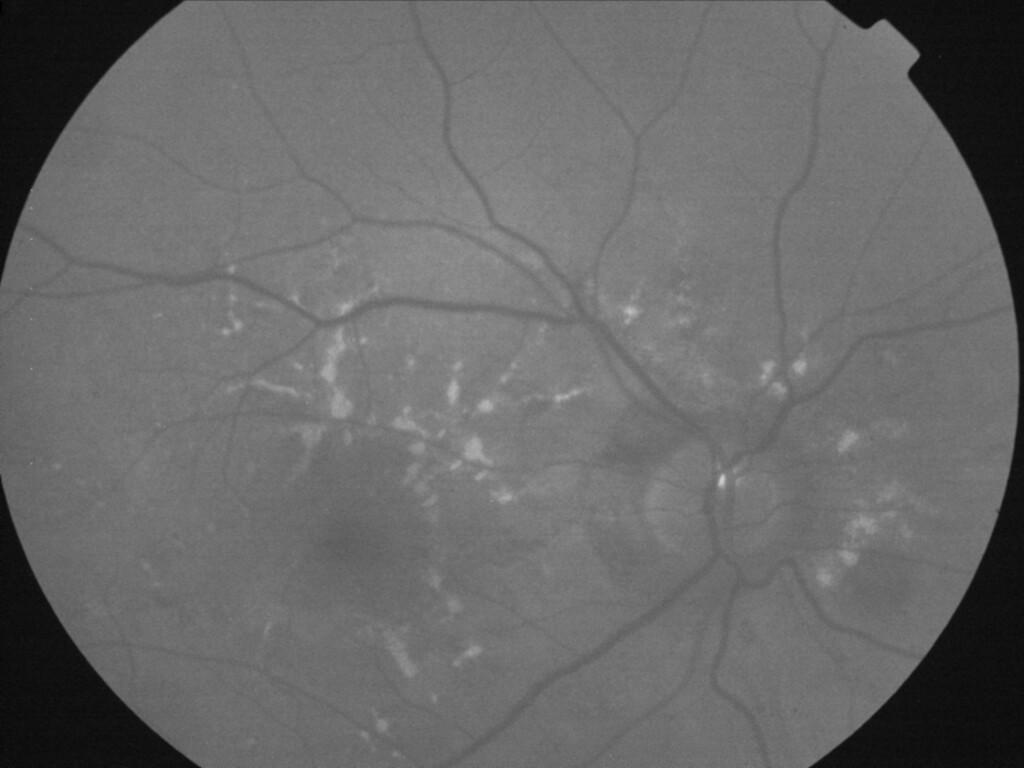

ASSOCIATION STRIES ANGIOIDES ET DYSROPHIE MACULAIRE RETICULEE

NEOVASCULARISATION